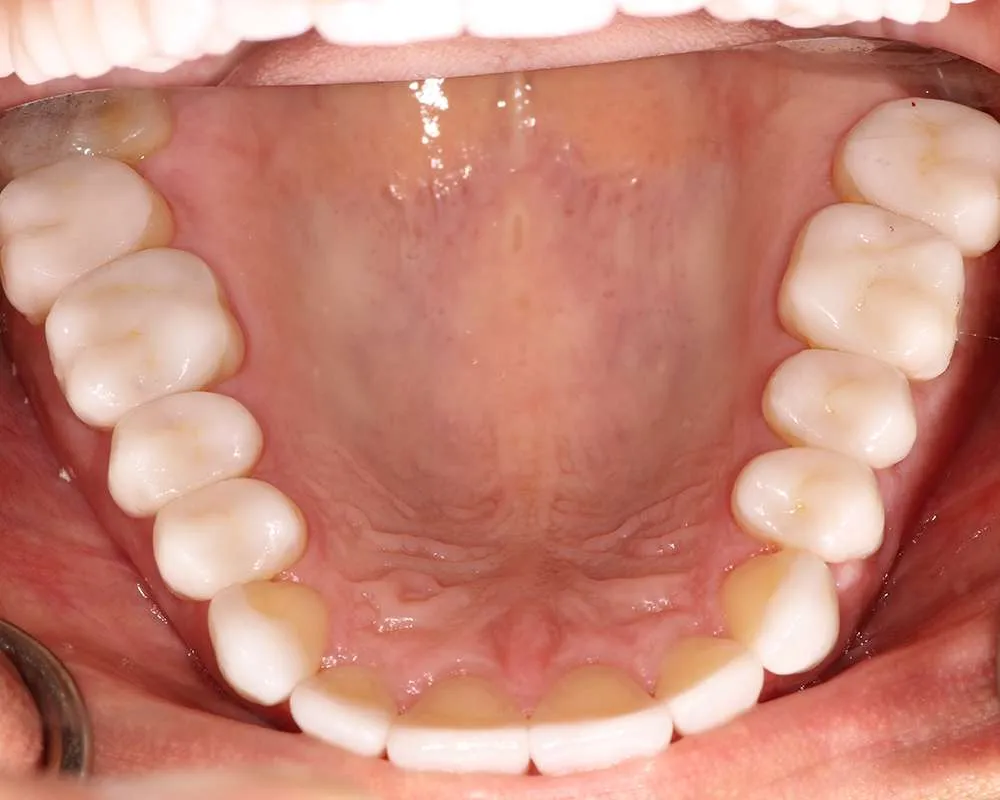

Real Stories, Real Results: Case Studies Showcasing How Our Personalized Approach Transforms Smiles and Lives

Witness the Remarkable Changes We Can Achieve